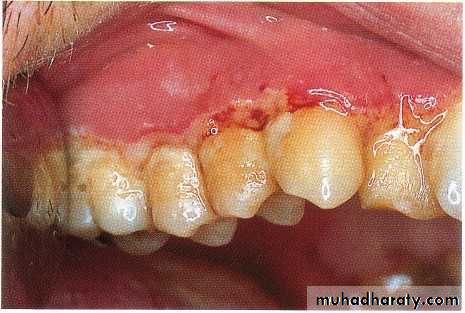

Puberty gingivitis is a distinctive type of gingivitis that occasionally develops in children in the prepubertal and pubertal period.11- to 14-year age group.

The enlargement of the gingival tissues is confined to the anterior segment and may be present in only one arch.

The gingival enlargement was marginal in distribution and, in the presence of local irritants, was characterized by prominent bulbous interproximal papillae

Treatment of puberty gingivitis should be directed toward improved oral hygiene, removal of all local irritants, adequate nutritional status

Severe cases of hyperplastic gingivitis that do not respond to local or systemic therapy should be treated by gingivoplasty